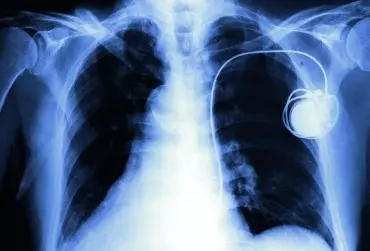

Wszczepienie urządzenia do stymulacji serca zmienia jakość życia chorych. Ważną i nieodzowną składową procesu leczenia jest sfera somatyczna, zgodnie z zasadą „Wszystko, co ma wpływ na pacjenta, wymaga uwzględnienia”. Wstępnie przeprowadzone badania w Poradni Stymulatorów Serca Wojewódzkiego Centrum Medycznego w Opolu pokazują, że jakość życia pacjentów po wszczepieniu stymulatora serca znacznie się poprawia i jej poziom w ocenie pacjentów jest zadowalający. Jednocześnie ocena jakości życia jest niższa w porównaniu z osobami zdrowymi. W procesie leczenia i rehabilitacji chorych ze stymulatorami serca do oceny tej użyto kwestionariusz WHOQOL-BREF (The World Health Organization Quality of Life).